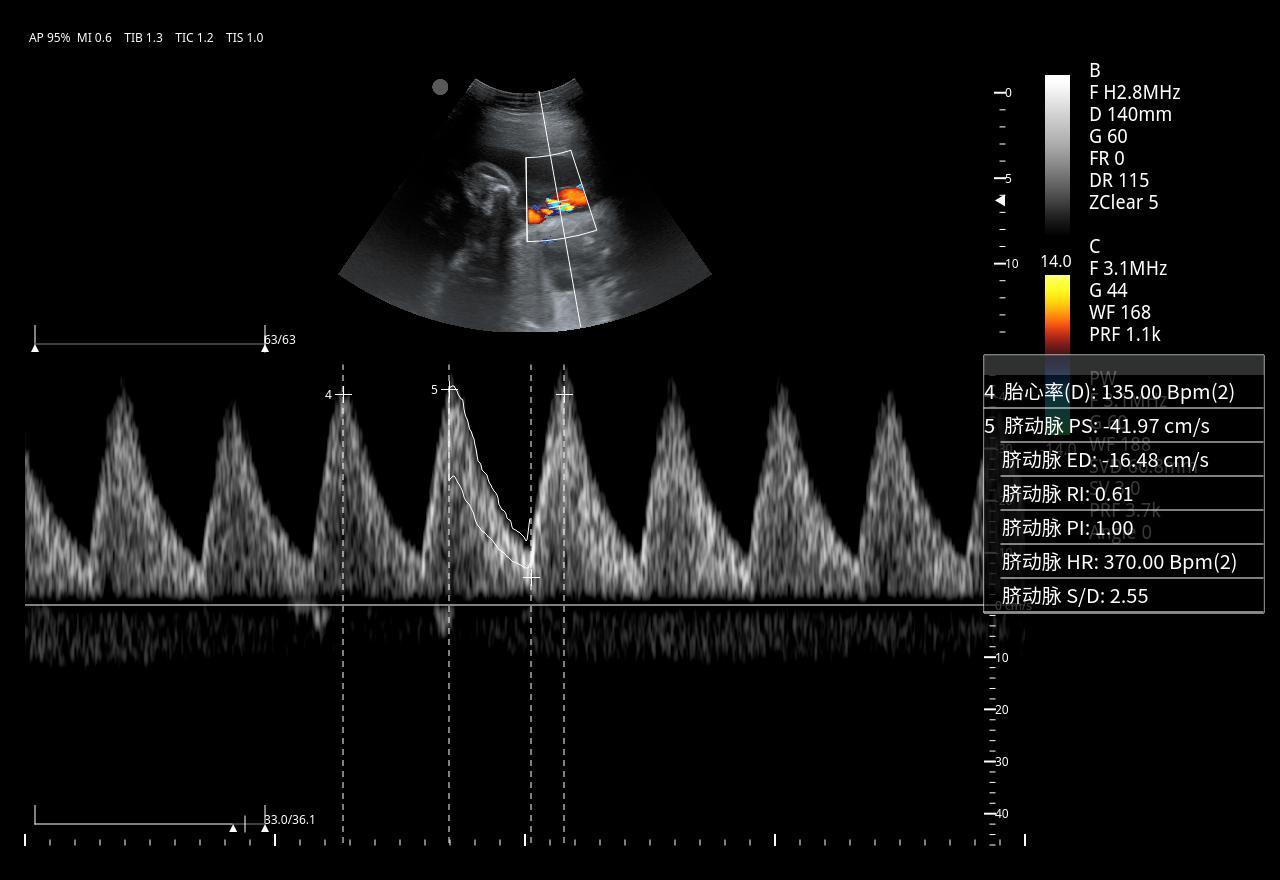

Imágenes clínicas extraordinarias